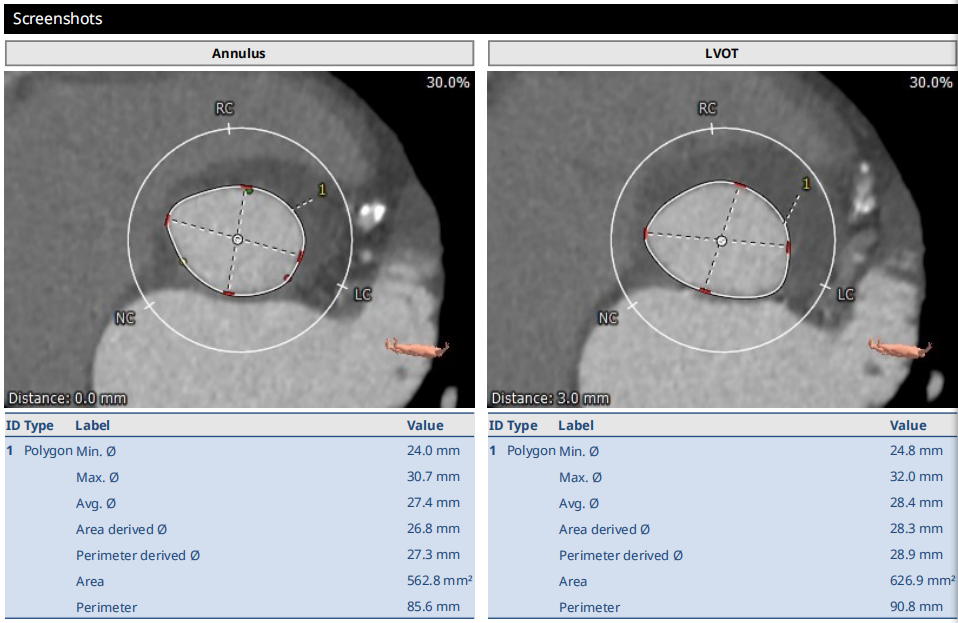

术前CT结果显示,主动脉瓣极重度钙化;主动脉瓣口面积562.8mm²,瓣环平均直径27.4mm,瓣环周长85.6mm;LVOT面积626.9mm²,LVOT平均直径28.4 mm。CT同时显示外周入路血管重度扭曲合并右侧腹主动脉瘤样病变。

图2 术前CT影像评估结果